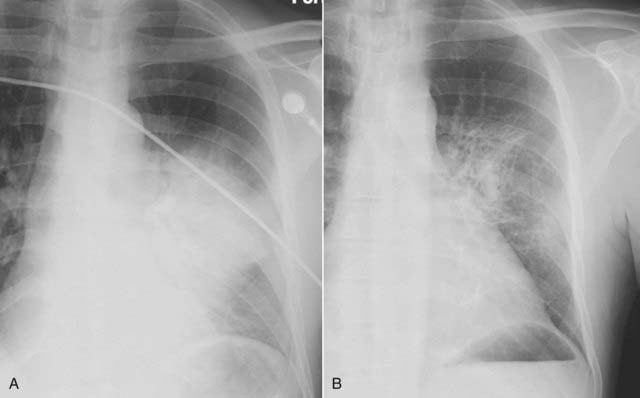

Figure 7-11 The spine sign.

Frontal (A) and lateral (B) views of the chest demonstrate airspace disease on the lateral projection (B) in the right lower lobe that may not be immediately apparent on the frontal projection (you can see the pneumonia in the right lower lobe in (A) (solid black arrow). Normally, the thoracic spine appears to get “blacker” as you view it from the neck to the diaphragm because there is less tissue for the x-ray beam to traverse just above the diaphragm than in the region of the shoulder girdle (see also Fig. 2-3). In this case, a right lower lobe pneumonia superimposed on the lower spine in the lateral view (solid white arrow) makes the spine appear “whiter” (more dense) just above the diaphragm. This is called the spine sign.